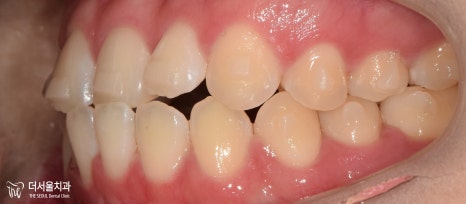

과연 구치부의 상태는 어떨까요?

교합면에서 확인해 보았더니

U자에 가까워야 될 악궁의 형태가

사각형에 가까워져 있었습니다.

하악 앞니 뻗침은 생각보다 심하네요.